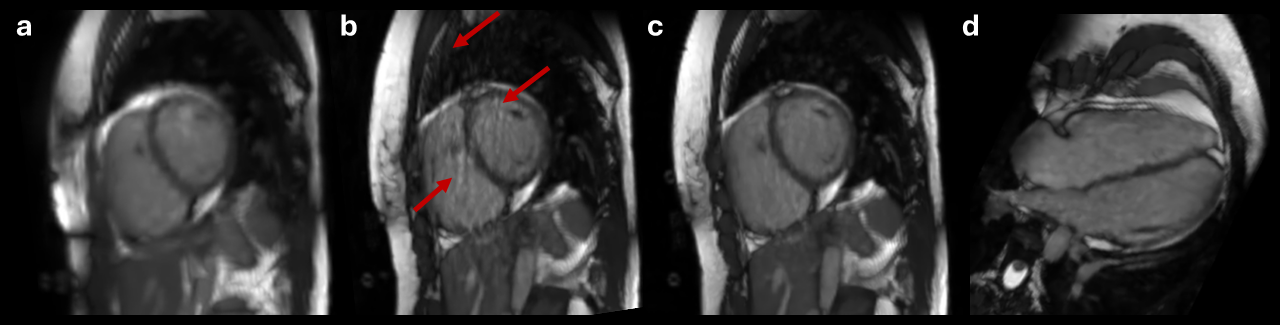

Diastolic short axis frames for a CHD patient with difficulty holding their breath. While the 15s 1-BH scan at 2.5mm was diagnostic (a), a 3-BH scan was added at 1.7mm isotropic resolution and 12s per BH (b-d). Images (c) and (d) show the 3-BH images in short axis and 4-chamber views with inter-BH motion compensation, and (b) shows the artifacts arising if the latter is omitted during reconstruction.

Diastolic short axis frames for a CHD patient with difficulty holding their breath. While the 15s 1-BH scan at 2.5mm was diagnostic (a), a 3-BH scan was added at 1.7mm isotropic resolution and 12s per BH (b-d). Images (c) and (d) show the 3-BH images in short axis and 4-chamber views with inter-BH motion compensation, and (b) shows the artifacts arising if the latter is omitted during reconstruction.

Diastolic short axis frames for a CHD patient with difficulty holding their breath. While the 15s 1-BH scan at 2.5mm was diagnostic (a), a 3-BH scan was added at 1.7mm isotropic resolution and 12s per BH (b-d). Images (c) and (d) show the 3-BH images in short axis and 4-chamber views with inter-BH motion compensation, and (b) shows the artifacts arising if the latter is omitted during reconstruction.

Diastolic short axis frames for a CHD patient with difficulty holding their breath. While the 15s 1-BH scan at 2.5mm was diagnostic (a), a 3-BH scan was added at 1.7mm isotropic resolution and 12s per BH (b-d). Images (c) and (d) show the 3-BH images in short axis and 4-chamber views with inter-BH motion compensation, and (b) shows the artifacts arising if the latter is omitted during reconstruction.